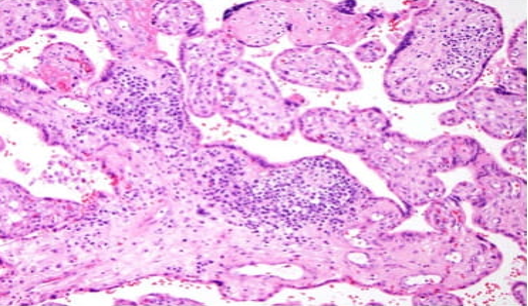

The four most common patterns of abnormal placentation/placental injury are:

4. Chronic villitis of unknown/immune etiology (non‑infectious)

Examples of abnormal immune placentation